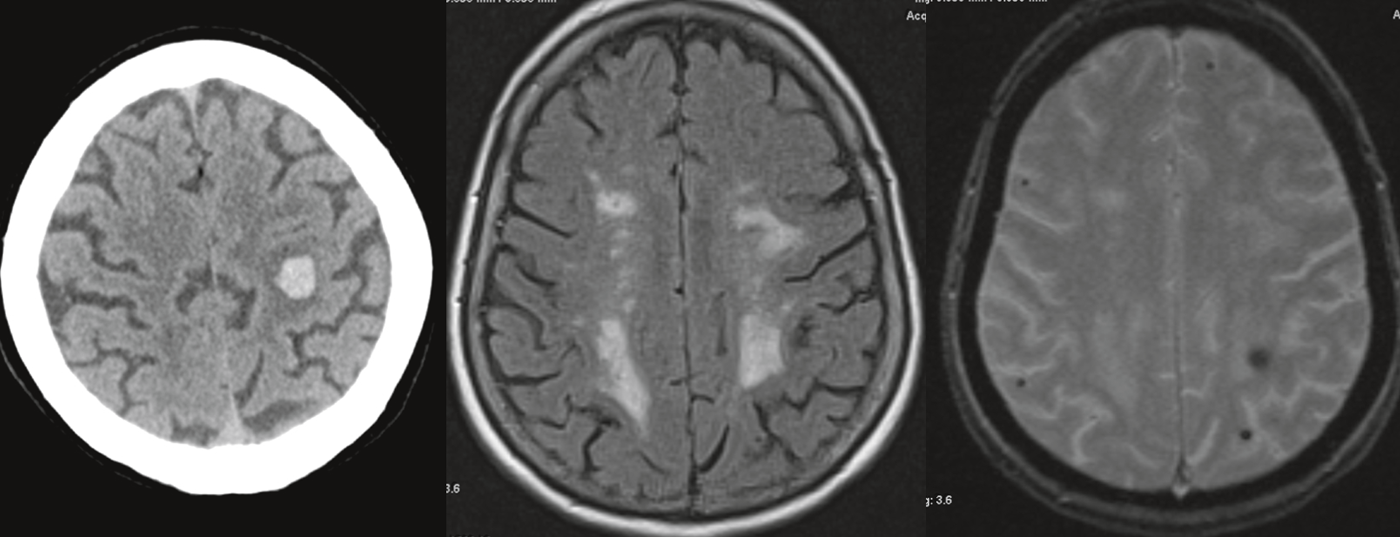

La causa più comune di VaD è la microangiopatia cerebrale, che è particolarmente associata all’ipertensione arteriosa. Oltre a questa forma sporadica, esistono anche forme ereditarie più rare di microangiopatia, in cui di solito c’è un’anamnesi familiare positiva di ictus cerebrale o di disturbi cognitivi – possibilmente senza fattori di rischio vascolare esistenti. Circa un terzo di tutti gli ictus ischemici sono causati da microangiopatia cerebrale. Queste portano a lesioni cerebrali ischemiche tipiche che possono essere visualizzate con la risonanza magnetica: Si verificano infarti lacunari sottocorticali. (Fig. 1a) nonché alterazioni vascolari leucoencefalopatiche nell’area del canale midollare. (Fig.1b). Inoltre, a volte si possono trovare microemorragie, che nella microangiopatia sono spesso localizzate nell’area delle strutture più profonde (ad esempio, i gangli della base).

La diagnosi per immagini mediante risonanza magnetica (tab. 3) mira da un lato a rilevare lesioni vascolari fresche (DWI) o più vecchie (T2/FLAIR) (fig. 1).

In particolare, occorre menzionare le tipiche lesioni ischemiche midollari che possono essere rilevate nella valutazione T2/FLAIR, che possono presentarsi nelle forme più varie fino a una leucoencefalopatia confluente. Questi cambiamenti sono comuni con l’età. Inoltre, c’è la questione dei difetti della sostanza lacunare (T1) e delle emorragie o microemorragie (T2*/SWI).